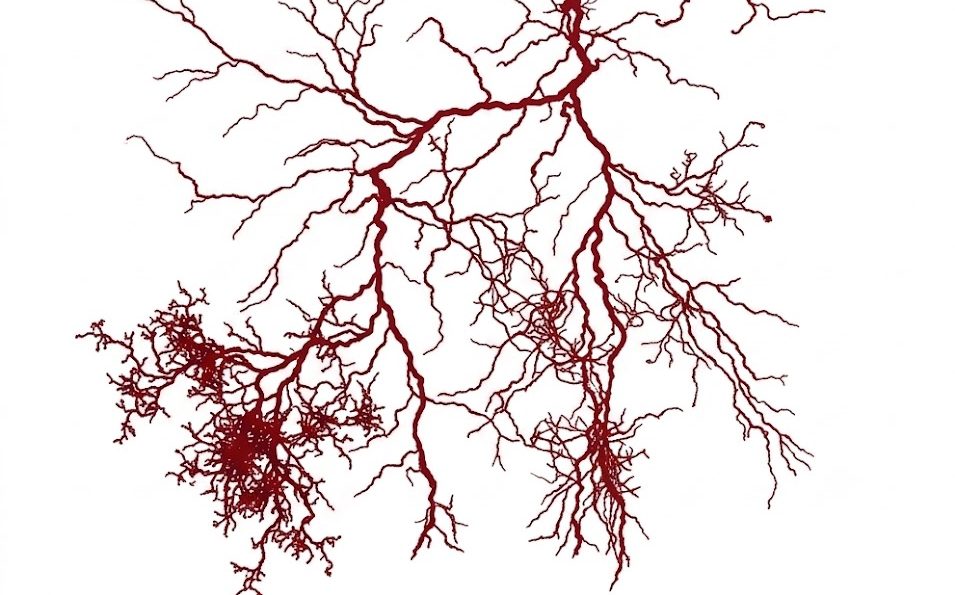

- Флебология